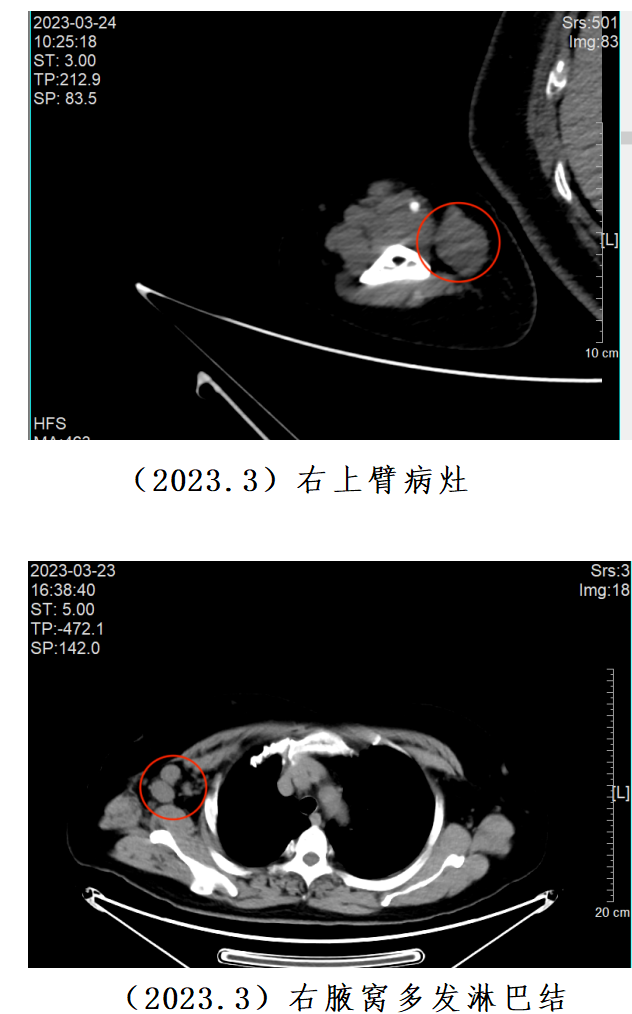

2023年3月,郭女士慕名求诊我院陈誉主任团队。在详细评估郭女士的病情后,陈誉主任认为其符合参加一项临床试验的条件,该试验旨在评估DNV3联合特瑞普利单抗在复发/转移皮肤罕见肿瘤患者中的安全性、耐受性、药代动力学特征和初步疗效,有可能极大缓解郭女士的病情。

最初,郭女士对参与临床研究抱有疑虑,担心未知的治疗方案可能带来的风险和不确定性。但随着时间的推移和治疗的深入,她的态度发生了明显变化。在6周的治疗后,她的肿瘤就缩小了30.26%。一年多来,郭女士相继完成了22周期的“DNV3+特瑞普利单抗”治疗,肿瘤持续稳定退缩。最近一次复查,肿瘤相比最初缩小了58.56%,病情取得阶段性控制。